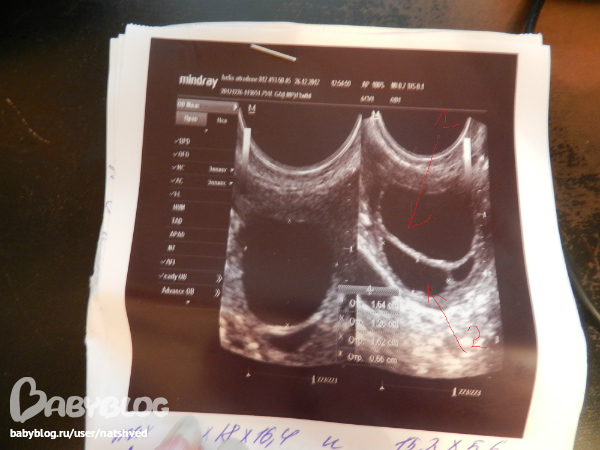

фоликул имеет четкие контуры, черное такое пятно

а ЖТ сероватое и контуры как с рябью

я думаю, что это ЖТ

вот фоликул

а вот жт

Очень похожи на ваши снимки.. даже описание про правый яичник))